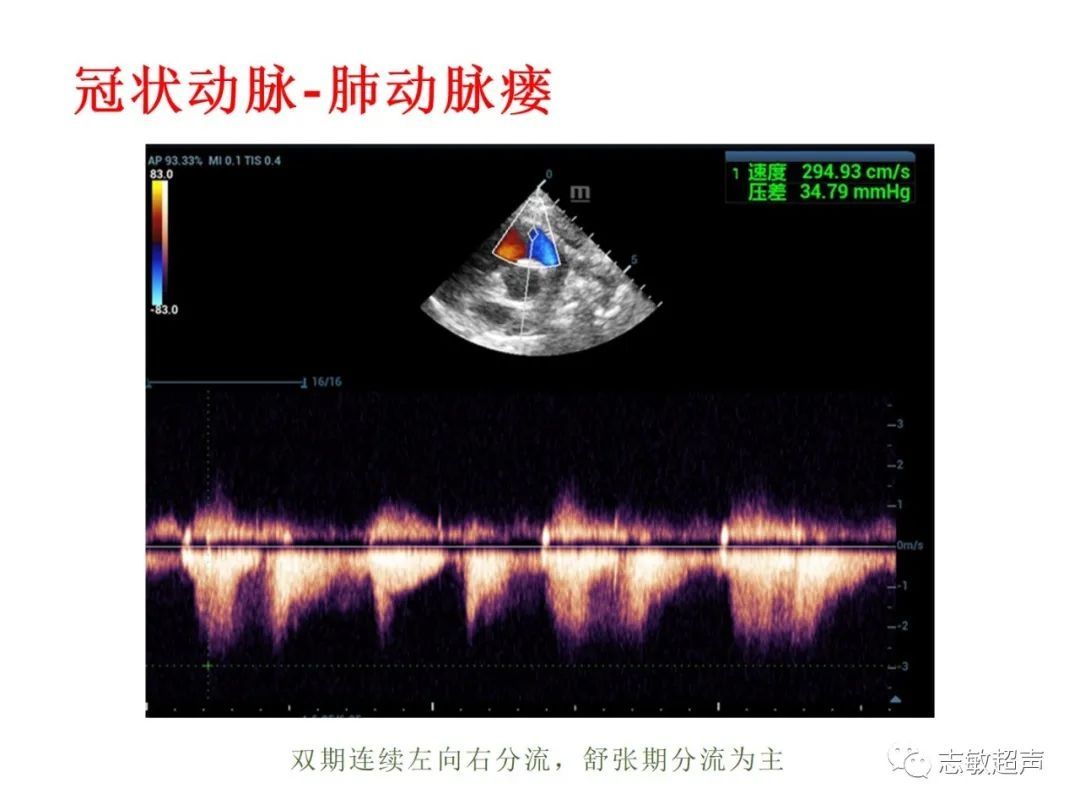

4.冠状动脉肺动脉瘘

冠状动脉-肺动脉瘘视频